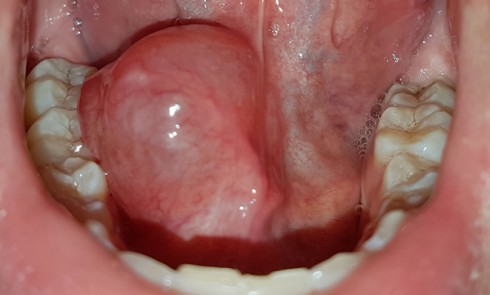

Article réservé à nos abonnés « Boule » sublinguale : la conduite à tenir

1. Quel est le diagnostic le plus probable ?a. Kyste dermoïdeb. Lymphangiomec. Kyste mucoïded. Abcès du plancher buccal d’origine dentairee. Lipome 2....